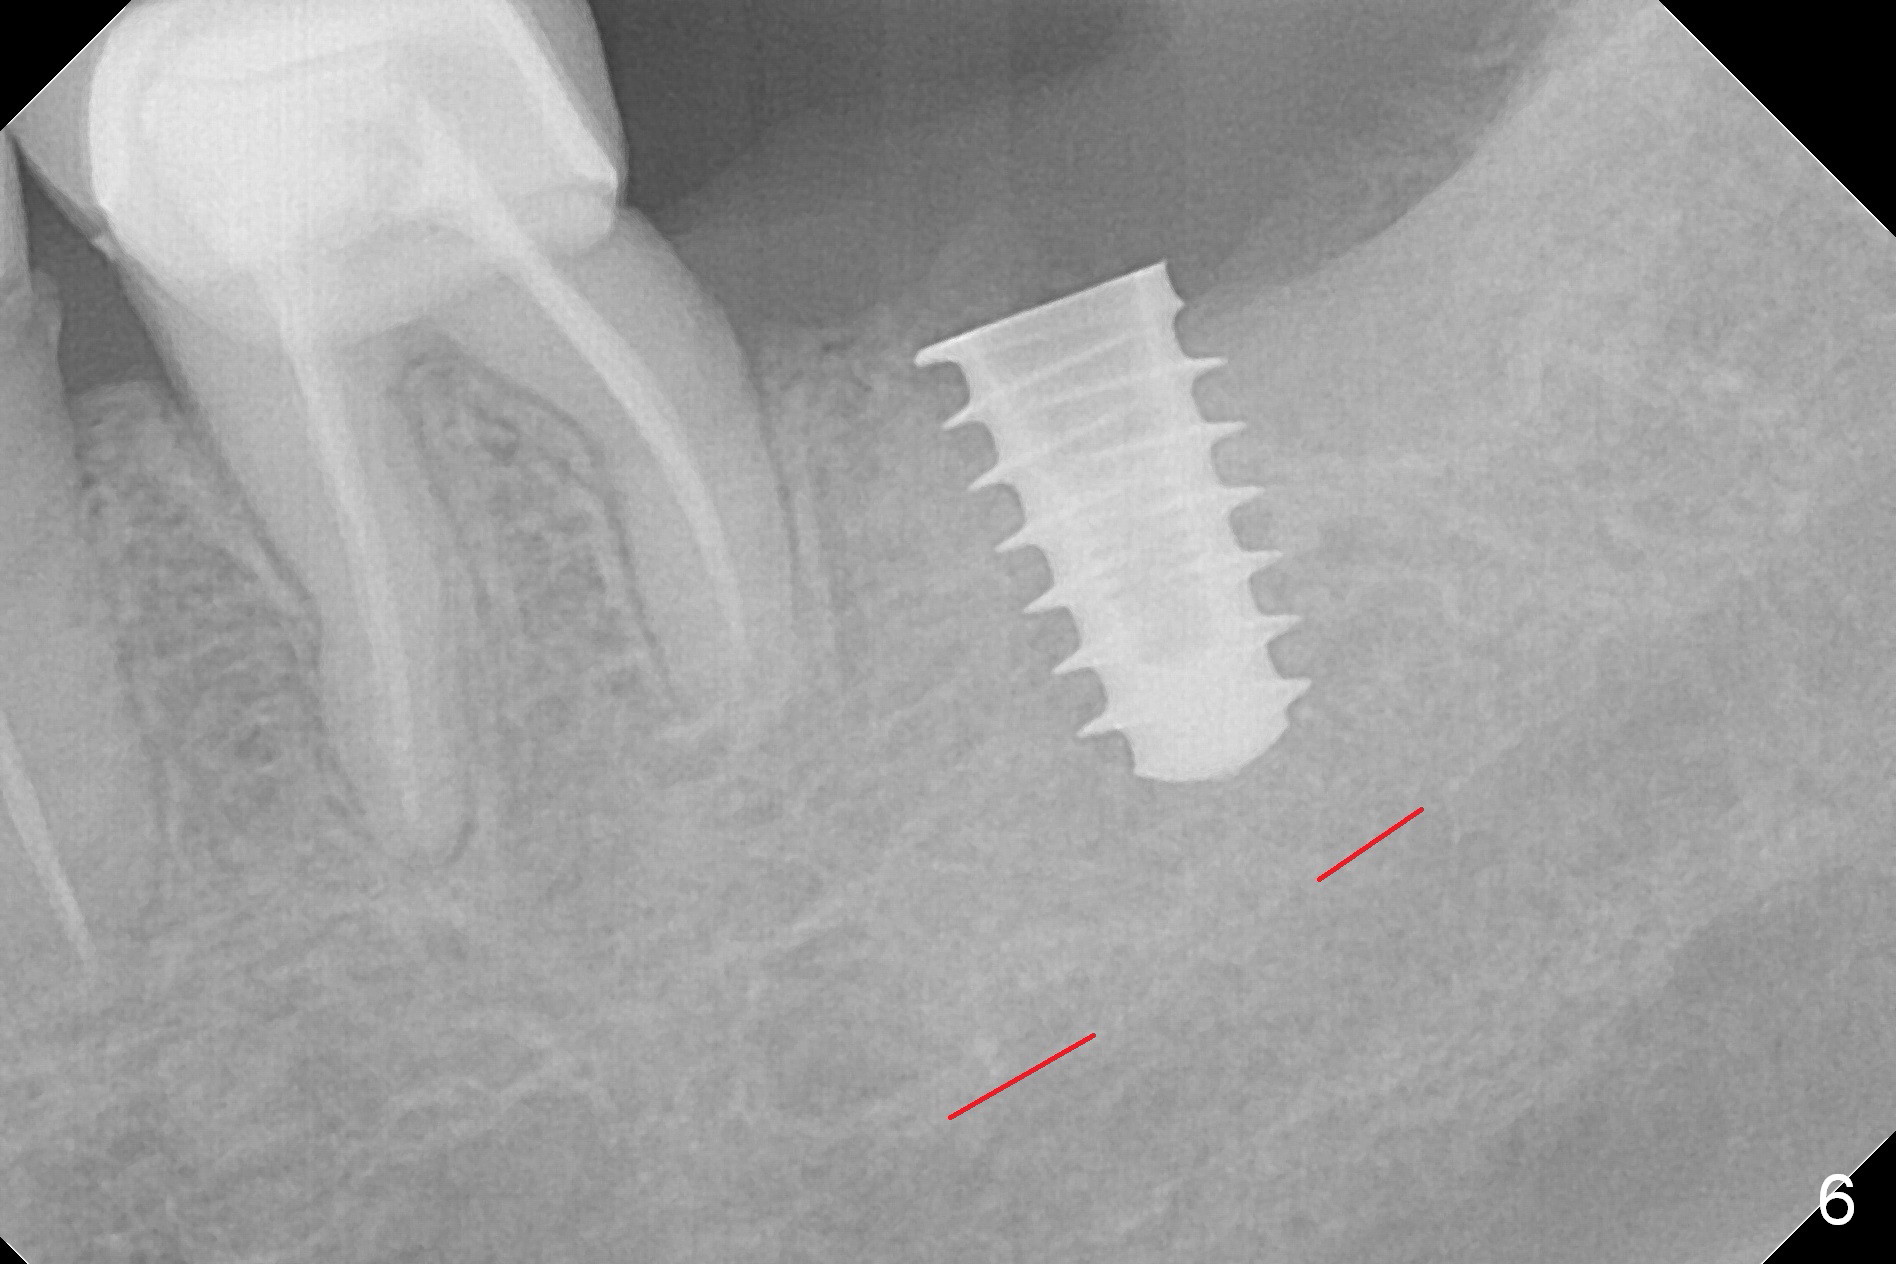

After 1.6 mm pilot drill (Fig.2) and 4.3 mm Magic Drill for 11 mm (gingival margin), a 4.5x11 mm dummy implant is placed with stability (Fig.3). Following Final Drill for 12/13 mm and 4.3 mm MD mesially, a 5x9 mm IBS implant is placed with 40 Ncm (Fig.4). Panoramic X-ray shows the placement is slightly supracrestal (Fig.5). In fact the implant is also placed slightly lingually. When the trajectory is changed, the implant loses stability. When a 5.5x9 mm implant is placed, no stability is achieved (Fig.6). After increase in osteotomy depth for 1-2 mm with MD 4.3 mm, the 5.5x9 mm implant barely obtains stability (~ 10 Ncm, Fig.7). Healing screw is placed. Osteogen plug is inserted in the distal portion of the socket; autogenous bone around the implant and Collagen plug to close the socket opening. Last suture and periodontal dressing are applied.

In fact, the mesial crest of the socket could be used as a more secure landmark (bony vs. soft tissue) for osteotomy depth (Fig.4 arrowhead) with drill stopper. To place the implant subcrestal, the initial osteotomy should be 1-2 mm deeper. When she returns 2 years 9 months postop, the wound has healed. The implant needs to be uncovered. Make sure to have clearance for a healing abutment. Use sensor 1 for PAs before and after uncover. The implant appears to be tilted distal. An angled abutment may be required. Take PA for seating confirmation. Guided surgery is preferable. The implant plateau is covered by the bone 2 years 9 months postop (Fig.8 *). The healing screw is removed with difficulty, while a 6x3 mm healing abutment is placed with resistance, probably related to interference from the distal crest (Fig.9 *). It is much easier with removal of the crest bone using surgical bur, because of clearance (Fig.10 *). It is the best to have a particular drill to remove the excess bone. There is no interference to insert and torque a 5x4(2) mm pair abutment 2 weeks post uncover (Fig.11). Due to poor trajectory (guide necessity) and tight proximal contact, the crown is not completely seated (Fig.12). However, the abutment screw is unlikely to get loose in the future.